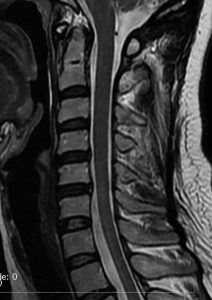

第4脳室腫瘍のMRI像

左は脳幹部腫瘍(退形成性神経節膠腫),右は小脳腫瘍(毛様細胞性星細胞腫)です。どちらも第4脳室を埋め尽くすように発育しています。これらはどちら側から発生したかが明瞭な例ですが,第4脳室腫瘍の中には脳幹部からか小脳からか解らないものもあります。でも多くは小脳側からです。脳幹部側からで注意しなければならないのは上衣腫と血管芽腫です。